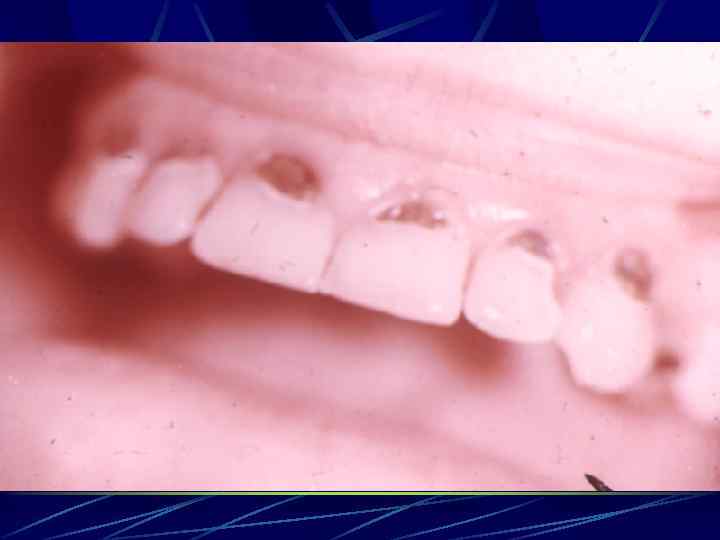

АНОМАЛИИ СТРОЕНИЯ И ПОРОКИ РАЗВИТИЯ ЗУБОВ «Тетрациклиновые» зубы молочного прикуса у ребенка 6 лет